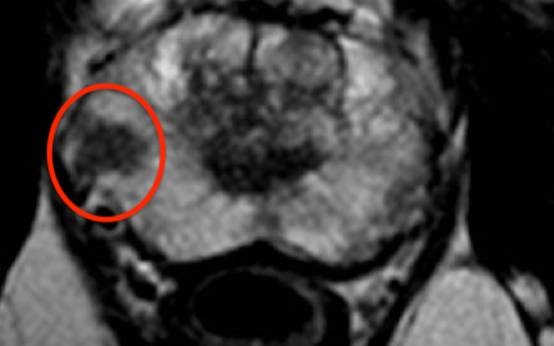

Στο Κέντρο Ελάχιστα Επεμβατικής Ουρολογίας του Ιατρικού Αθηνών έχουμε εφαρμόσει τις πλέον προχωρημένες διαγνωστικές και απαραίτητες εξετάσεις στις περιπτώσεις υποψίας καρκίνου προστάτη. Όταν το PSA ή/και η Δακτυλική εξέταση (ΔΕΠ) θέτουν τέτοιες υπόνοιες, ο ασθενής χρήζει μιας ειδικής μαγνητικής, της Πολυπαραμετρικής Μαγνητικής Τομογραφίας Προστάτη. Αυτή αποτελεί τη μοναδική απεικονιστική εξέταση που μπορεί να ανιχνεύσει κλινικά σημαντική εστία καρκίνου προστάτη ακόμα και διαμέτρου λίγων χιλιοστών.

Με οδηγό την πολυπαραμετρική μαγνητική, θα ακολουθήσει η Βιοψία προστάτη. Αυτή θα πρέπει να λαμβάνεται όχι μόνο από κάθε περιοχή του προστάτη, αλλά και στοχευμένα από την ύποπτη περιοχή που υποδεικνύει η μαγνητική (σύστημα fusion).

- Την εξονυχιστική μελέτη της πολυπαραμετρικής μαγνητικής τομογραφίας του προστάτη σε συνδυασμό με την τοπογραφία των θετικών βιοψιών (όρια του όγκου από την κάψα, νόσος σε περισσότερες εστίες και πού στον προστάτη, απόσταση του καρκίνου από τα αγγειονευρώδη δεμάτια του προστάτη υπεύθυνα για τη στύση κλπ)